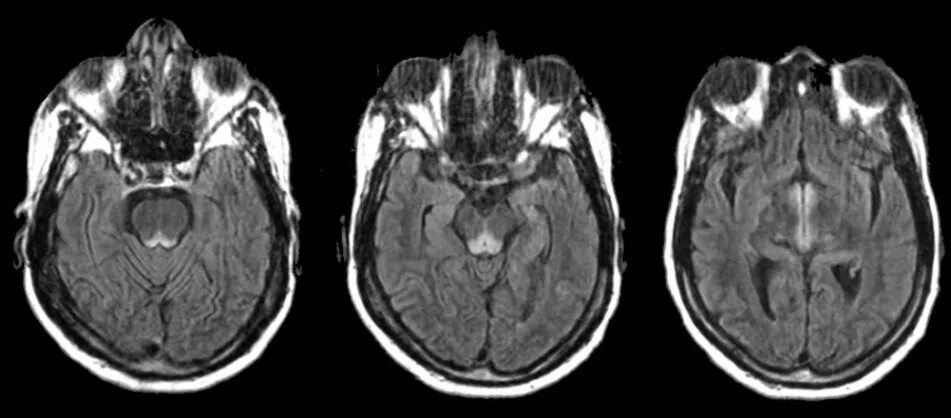

Гая вернике